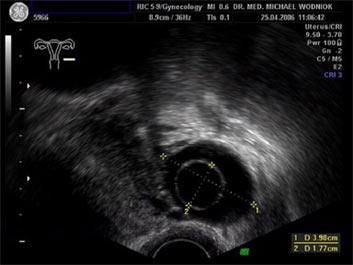

Hochauflösende Ultraschalluntersuchungen in Kombination mit der 3D-4D Technik werden in unserer Praxis routinemäßig durchgeführt. Dabei werden im Rahmen der Vorsorgeuntersuchung, sowie bei reinen vorsorglichen Ultraschalluntersuchungen auf Wunsch, auffällige Tastbefunde und noch unentdeckte Befunde weiter sonografisch abgeklärt. Bei zweifelhaften Befunden der Brüstdrüsen oder von Organen der inneren Genitalien kann der zusätzliche Einsatz der Farbdopplertechnik sehr hilfreich sein. Dabei stellt diese Technik bildlich sehr genau den Blutfluss, die Flussgeschwindigkeit, den Blutflusswiderstand sowie die Blutflussrichtung aller Blutgefässe dar. Die Interpretation dieser Ergebnisse fließt als zusätzlicher „Marker“ in die Entscheidung für das weitere klinische Vorgehen ein. Ein zunächst als völlig unauffällig eingestufter Ultraschallbefund eines zystischen Befundes im Eierstock wird bei einem unerwartet auffälligen Blutfluss an der inneren Zystenwand eine zeitnahe weitere Abklärung zu Folge haben. ![]() ![]() ![]() ![]() |